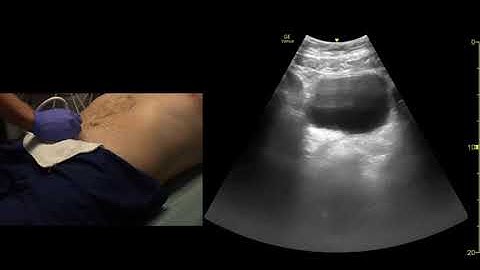

How to perform FAST exam/only 3 minute